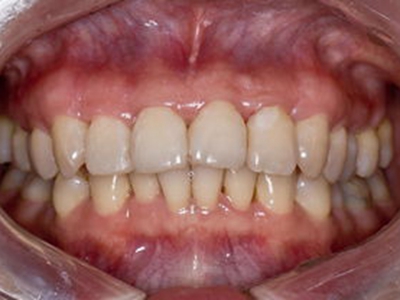

牙龈退缩牙龈萎缩露出牙根图

牙龈退缩发作于上排尖牙和磨牙处,导致牙根暴露在外,伴有牙齿松动、口臭、牙根面敏感等症状,是由于刷牙不当、牙周炎等因素引起。